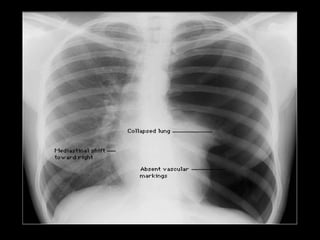

Spannungspneumothorax

„Klinisch präsentiert sich ein Pneumothorax in 90% der Fälle durch

Thoraxschmerzen und durch Dyspnoe in 80% der Fälle. Tritt durch einen

Ventilmechanismus ein Spannungspneumothorax auf, kommen Zeichen der

hämodynamischen Beeinträchtigung und der respiratorischen Insuffizienz hinzu.“

„Die rasche Entlastung des Spannungspneumothorax und Drainage der Luft aus

dem Pleuraraum haben höchste Priorität.“